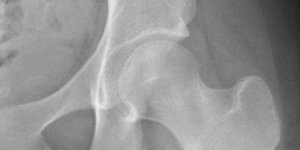

Hip Stress Fracture in a Runner | Cases

Published on May 4, 2020

19 female, triathlete c/o groin pain. started after a spike in training load over a 2 month period. 60km a week bike, 40-50 km running, 2-3 swims. Exam Antalgic gait Pain with FADIR and IR of hip NAD on X-ray. x-ray MRI MRI – Coronal Views What is the pathophysiology of a stress fracture?